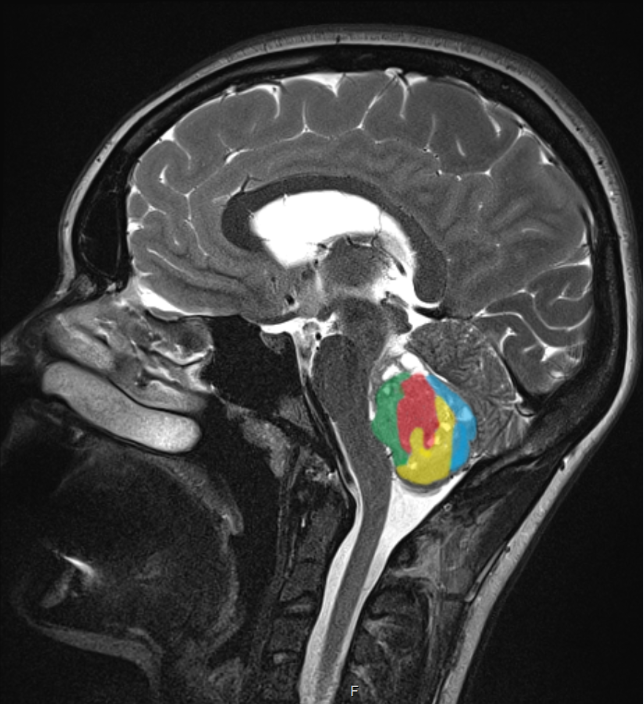

„Medulloblastome (farbig) gehören bei Kleinkindern zu den häufigsten bösartigen Hirntumoren.“ Marc Remke /Universitätsklinikum Düsseldorf

Molekulare Muster werden bei Hirntumoren immer häufiger eingesetzt, um das Ansprechen auf eine Krebstherapie vorhersagen und Patienten die passende Therapie empfehlen zu können. „Bei kindlichen Hirntumoren, dem Medulloblastom, sind die Prognosen in vielen Fällen sehr zuverlässig“, erklärt Dr. Marc Remke, der am Universitätsklinikum Düsseldorf die Nachwuchsgruppe für Pädiatrische Neuroonkologie des Deutschen Konsortiums für Translationale Krebsforschung (DKTK) leitet. „Ist beispielsweise der sogenannte Wnt-Signalweg im Tumor aktiviert, haben Patienten mit den gängigen Standardtherapien eine exzellente Heilungschance.“ Seit 2016 sind diese und andere molekulare Klassifizierungen von Hirntumoren auch von der Weltgesundheitsorganisation WHO anerkannt.

Voraussetzung für die Zuverlässigkeit der Methoden ist allerdings die eindeutige Ermittlung des genetischen Tumorprofils. Genau hier liegt die Herausforderung, denn die Zellen eines Hirntumors haben oft mehr Unterschiede als Gemeinsamkeiten, wie Marc Remke mit kanadischen Forscherkollegen von der Universität Toronto, des Hospital for Sick Children und von der Cancer Agency Britisch Columbia herausfand. Das Team zeigte erstmalig, dass sowohl Hirntumoren bei Erwachsenen (hochgradige Gliome) als auch kindliche Hirntumoren (Medulloblastome) aus genetisch unterschiedlichen Regionen bestehen. Die Forscher sezierten Tumorproben von insgesamt 35 Patienten und untersuchten die räumliche Verteilung genetischer Veränderungen, die bei der Tumorentwicklung eine Rolle spielen. „Die verschiedenen Tumorregionen unterschieden sich durch einzelne Mutationen und in der Kopienzahl bestimmter Gene im Erbgut der Krebszelle“, erläutert Remke. „Sowohl bei den kindlichen Medulloblastomen als auch bei den Gliomen waren daher zwei oder mehrere Biopsien notwendig, um zu ermitteln, ob die genetischen Veränderungen im gesamten Tumor vorkommen.“